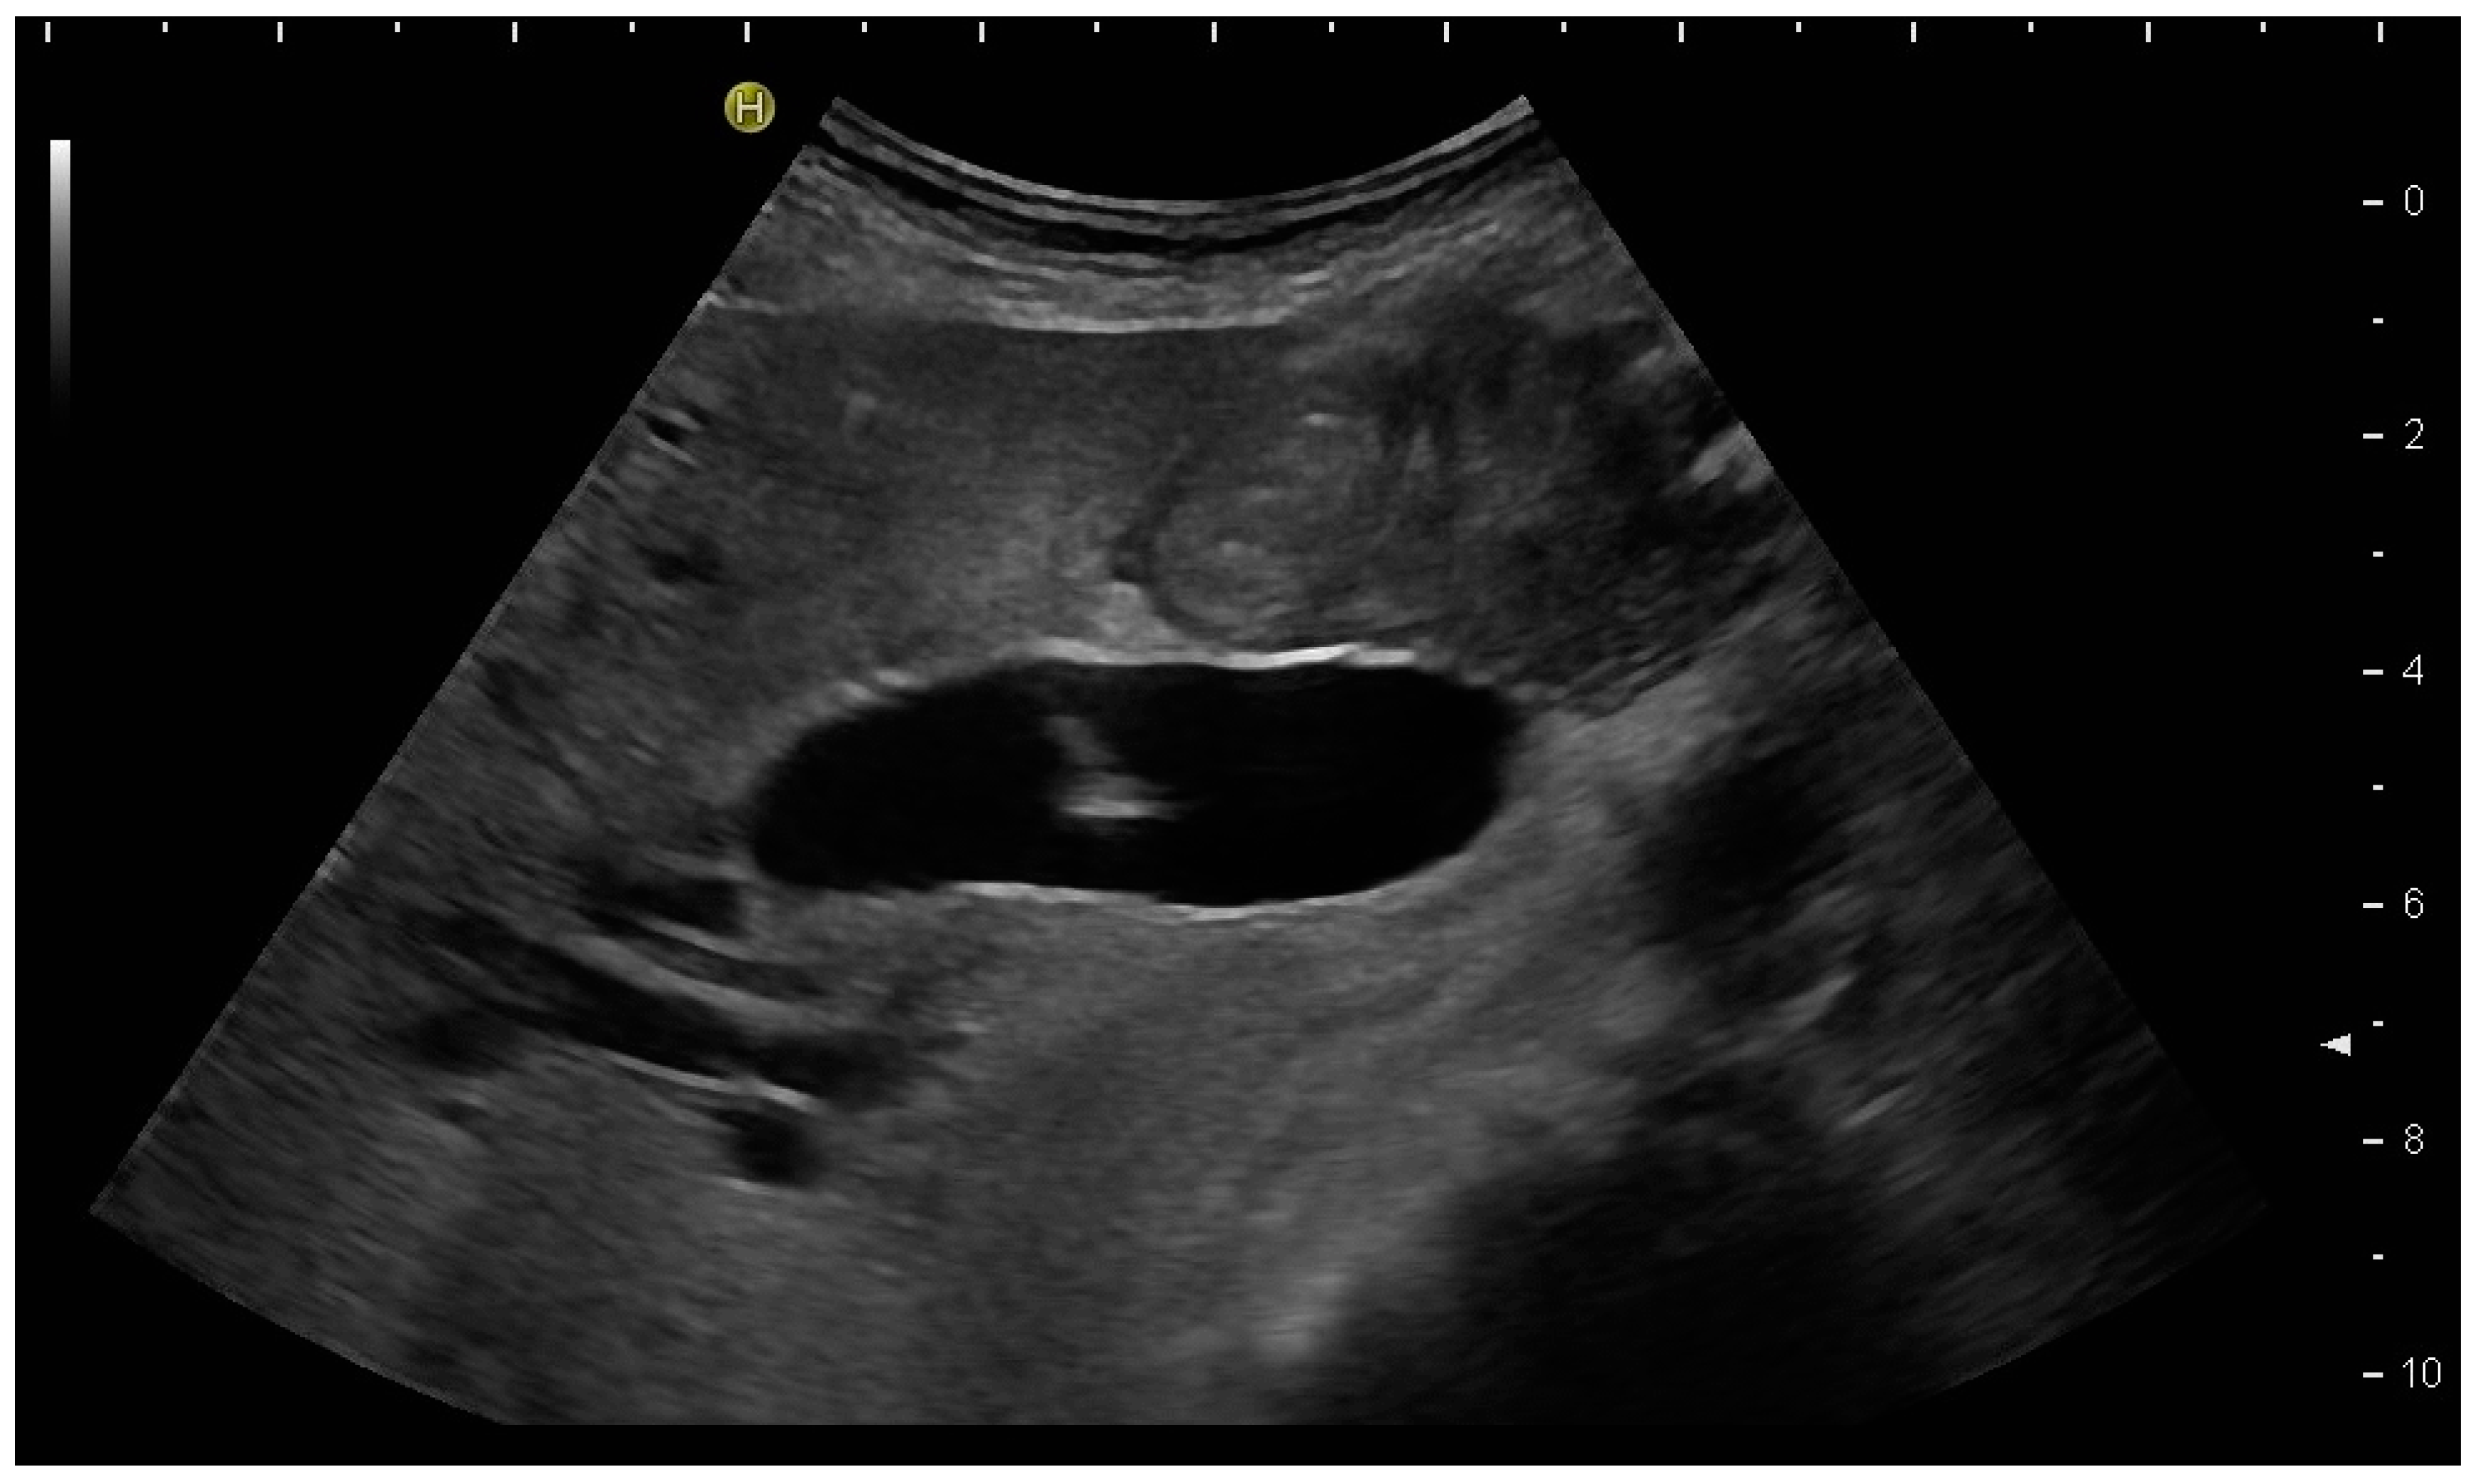

Most authors recommend a transhepatic approach in order to prevent biliary leakage to the abdominal cavity during drainage or after removal of drainage [43,55,56,76,77] (Figure 9).

(a) Transhepatic puncture of an inflamed gall bladder in the in-plane technique. The Chiba needle is depicted well; (b) A few days later, laparoscopic cholecystectomy was performed. The drainage ran through Segment V of the liver. It was removed without provoking biliary leakage from the liver parenchyma.

The consideration is that a perforation in the hepatic surface of the gallbladder will be covered by the liver tissue after the removal of the drain. However, retrospective analyses comparing the transhepatic route with the transperitoneal (i.e., nontranshepatic) access (Figure 10) report no differences in the complication rates [58,78,79].

PGBD without passing the liver and using the trocar technique: straightened drainage passes right below the lower liver margin into the gallbladder.

Again, the “in plane” approach is recommended to depict the needle in real time and continuously on its way. This is mandatory because iatrogenic perforation of the posterior gallbladder wall must be avoided. Both the drainage techniques, Seldinger (Figure 11a–c) and trocar (direct puncture, cf. Figure 10), may be used, depending on the physician’s preferences [43,58].

When using the Seldinger technique, first a Chiba needle is placed in the gallbladder (a), through which a 0.035” guide wire with bended tip is inserted (b). Plastic pigtail drainage (c) is then advanced over the guide wire.

We recommend the use of 8F or 10F pigtail drainage. If it is inserted using Seldinger’s technique, dilatation is not necessary. If the guide wire is confirmed to be in the correct place and is secured well, drainage placement can be performed without US visualisation [43,76].